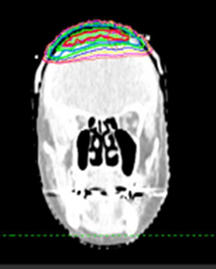

Figure 1F Template marks of repigmented hair were superimposed on the patient’s original planning scan. Red volume is right sided and blue volume is left sided. Axial slice.

Figure 1G Template marks of repigmented hair were superimposed on the patient’s original planning scan. Red volume is right sided and blue volume is left sided. Coronal slice.